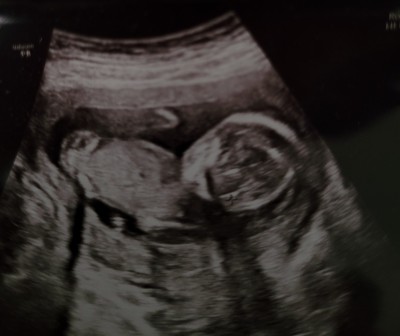

16. hafta kesin kız bacak arası boş dedi, 17. hafta emin degilim erkek de olabilir dedi. 16. haftadan sonra cinsiyet değişir mi gerçekten?

Gebelik haftası 17

Canım bilmiyorum ama erkek hemen gösterir belli olur diyolar ben 12 haftalıkta ikili teste öğrendim erkek dedi  tam emin olmak için 16 da gel dedi ondada erkek dedi 27 haftaliga kadar  her gittiğimde bebek erkek dedi hep söyledi  yanılma olur diye başka doktora gittim oda erkek dedi 34 haftalık hamileyim erkek bekliyorum

Benim 19.haftaya kadar gostermiyo pozisyon uygun drgil dediler ozellikle bakti dr uzun uzun bos goruyorum kiz dedi, 4gun sonra baska dr erkek dedi. Tmm saglikli olsun tabi de insan bilmek istiyo. Haftam kucuk fln da degildi 19+1 kiz 19+5 erkek. Bi taneside 4d bakmadi sozde ozele gidiyorum hala net degil benim kafamda. Sonrada dogum vakti aa goremedik eli sandik kolu sandik kordon sandik sacma sacma bi suru sey duyuyoruz